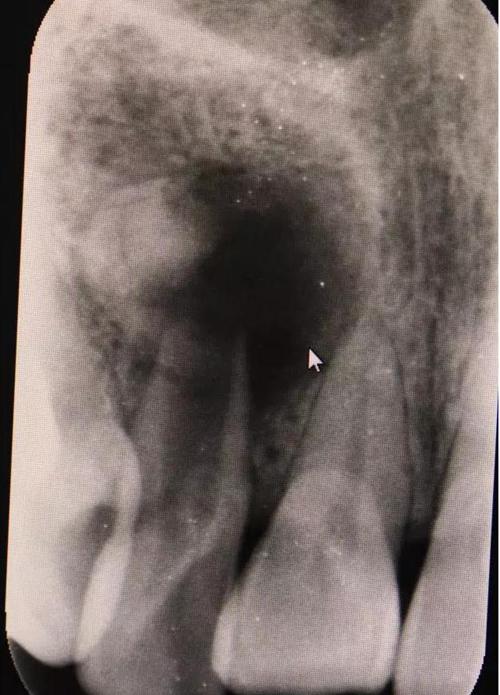

圖1.術前的根尖片影像檢查:12根管粗大、根尖未形成。根尖下方有一橢圓形囊腔,囊內(nèi)有牙。